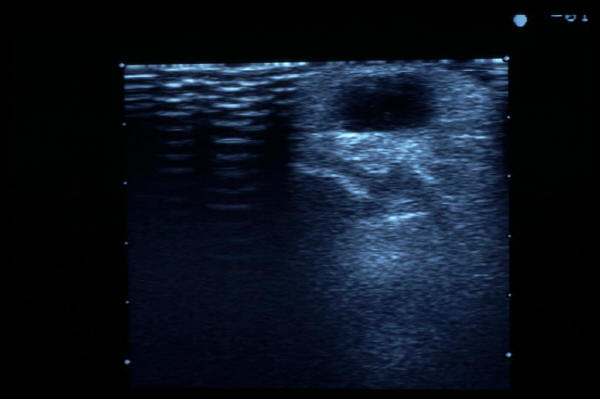

Quiste sinovial muñeca. Eco.